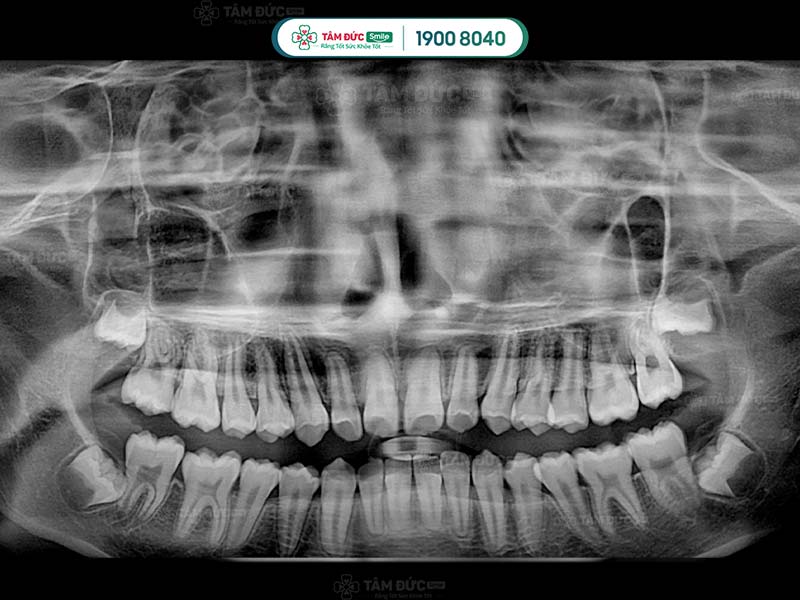

10.1. Chụp phim và tư vấn

Đây là bước quan trọng nhất trong quy trình nhổ răng khôn an toàn. Quý khách cần chụp phim X-quang để bác sĩ xác định vị trí và tư thế của răng khôn. Qua đó, bác sĩ dễ dàng đưa ra phương án nhổ răng an toàn nhất.